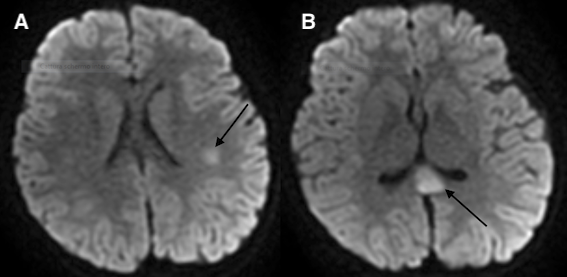

I dati di imaging sono riportati nella Tabella IV. La polmonite interstiziale postero-basale subpleurica è stato il reperto TC di maggiore riscontro (55% dei casi). Cinque pazienti hanno presentato versamento peritoneale associato o meno a linfoadenite mesenterica ed epatosplenomegalia. L’ecocardiogramma è stato eseguito in tutti i bambini, con evidenza di versamento pericardico nel 22% dei casi, insufficienza mitralica nel 33% e insufficienza tricuspidalica nel 22%. In un paziente è stato rilevato un aumento della birifrangenza coronarica. In nessun paziente è stata descritta una riduzione della frazione di eiezione. La cardio-RM è stata eseguita in post-dimissione nei 2 pazienti che hanno presentato bradicardia sinusale: in entrambi è stata confermata una funzione sistolica nella norma, in assenza di segni indicativi di edema e/o fibrosi del miocardio. La RM encefalo è stata eseguita in un paziente con sintomi neurologici, rilevando la presenza di lesioni compatibili con encefalomielite acuta disseminata (ADEM).

Nel periodo compreso tra marzo 2020 e gennaio 2021, presso il nostro Centro di Malattie Infettive Pediatriche, sono stati ricoverati 80 bambini affetti da Covid-19, di cui 9 (11%) con MIS-C; la quasi totalità dei casi si è verificata nel periodo compreso tra settembre e gennaio, verosimilmente a causa della maggiore circolazione del virus durante questi mesi nella nostra area geografica. In accordo ai dati della letteratura, si tratta di una patologia che interessa prevalentemente i soggetti in età scolare. Alla febbre si sono associati più frequentemente sintomi gastrointestinali (dolore addominale e diarrea) e mucocutanei (rash diffuso con coinvolgimento palmo-plantare, iperemia delle labbra e del faringe)6-8. Solo 2 pazienti hanno presentato sintomi cardiologici (ipotensione), associati in un caso a incremento degli enzimi cardiaci. Questo dato si discosta da quanto evidenziato in letteratura: in più della metà dei casi pubblicati è stato rilevato un coinvolgimento cardiaco, che ha richiesto talvolta un supporto ventilatorio e con inotropi6-8. Nella nostra casistica nessun paziente ha necessitato di ricovero in terapia intensiva. Sintomi neurologici sono stati riscontrati in 2 pazienti: in uno è stata posta diagnosi di ADEM post Covid-19. Si tratta di una condizione rara associata al SARS-CoV-2, con pochi casi pediatrici documentati in letteratura9-11. L’interessamento cutaneo è prevalente nel gruppo di soggetti in età prescolare, mentre quello cardiaco e di altri organi è più comune nei pazienti di età superiore ai 5 anni; la sintomatologia gastrointestinale, invece, si presenta in egual misura nei due gruppi di età (Tabella V).

In accordo ai criteri diagnostici elencati in Tabella I, la diagnosi di MIS-C richiede la presenza del coinvolgimento di almeno 2 o più organi; gli esami strumentali svolgono quindi un ruolo fondamentale, soprattutto nel caso in cui l’interessamento d’organo sia clinicamente silente. Attualmente sono scarse le evidenze in letteratura riguardanti gli aspetti radiologici dei pazienti con MIS-C. I reperti toracici più frequentemente riportati sono la cardiomegalia, il coinvolgimento polmonare con aspetto a vetro smerigliato bilateralmente più o meno associato a consolidamento parenchimale (come osservato in 5 dei nostri pazienti - Figura 1), il versamento pleurico (presente anche in 4 dei nostri bambini), l’edema polmonare, l’embolia polmonare, il versamento pericardico (evidenziato altresì in 2 dei nostri bambini)13,14. Nei pazienti con MIS-C, l’imaging cardiaco (ecocardiografia e RM) può mostrare una ridotta frazione di eiezione del ventricolo sinistro, miocardite, pancardite, cardiomiopatia dilatativa e versamento pericardico15; un dato di rilievo nella nostra casistica è stato il riscontro di valvulopatia in 5 dei nostri pazienti (55%): abbiamo riscontrato 2 casi di insufficienza tricuspidalica e 3 di insufficienza mitralica, tutte di natura transitoria. Tra i reperti radiologici extratoracici, i riscontri più frequenti sono stati la linfoadenopatia mesenterica (rilevata in 2 dei nostri pazienti - Figura 2), l’ispessimento della parete intestinale con interessamento dell’ileo terminale e del cieco, l’epatomegalia, l’edema peri-portale (osservato anche in un nostro caso), l’edema della colecisti (come in uno dei nostri pazienti), i reni iperecogeni e gli infarti splenici15. La RM cerebrale nei pazienti con MIS-C può rilevare: ictus ischemico, encefalite, ADEM (rilevata anche nella nostra casistica - Figura 3) o leucoencefalite emorragica acuta15.